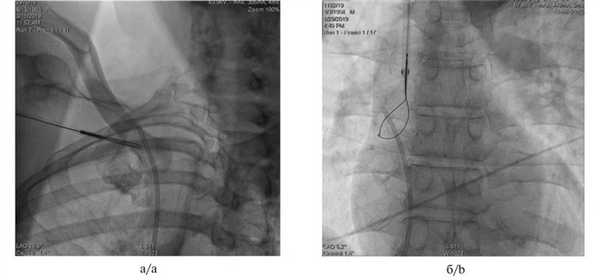

Диагноз отсоединения катетера или его отрыва ставили на основании клинической картины (боль при введении или невозможность ввести препарат, отсутствие обратного тока крови) и подтверждали при помощи ультразвукового (рис. 1) Рис. 1. Эхокардиограмма. Инородное тело в полости правого предсердия (указано стрелкой). или рентгенологического (рис. 2) Рис. 2. Рентгенограммы органов грудной клетки. а — инородное тело в правом предсердии (указано стрелкой); б — обрыв катетера на уровне ключицы (синдром pinch-off, указано стрелкой). исследования.

У 3 больных с миграцией катетера, переведенных из других лечебных учреждений, в условиях рентгенооперационной выполнена операция эндоваскулярного удаления инородного тела (рис. 3). Рис. 3. Рентгенограммы органов грудной клетки во время удаления катетера с использованием ретривера с крючками (grab retriever) — а и ретривера петля (loop retriever) — б. Во всех наблюдениях использован доступ через правую бедренную вену. Его пришлось дополнить доступом через правую подключичную вену в одном наблюдении и через правую внутреннюю яремную вену в другом. Использованы ретривер петля (loop retriever) и ретривер с крючками (grab retriever). После нескольких попыток инородное тело удалось захватить ретривером и удалить через доступ в бедренной вене. Послеоперационный период протекал без осложнений, больные выписаны на 2—3-и сутки.